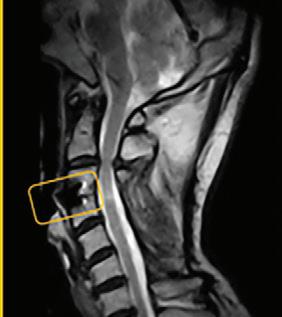

What a weight-bearing MRI reveals vs. a Supine MRI

G-scan Brio Reveals What Supine MRI Misses

Conventional MRI may not demonstrate the pathology related to these symptoms, but G-scan Brio gives you a new point of view so you can accurately diagnose MSK pathologies affected by weight-bearing position.

More Detail, Better Accuracy, Greater Confidence

G-scan Brio: Adds Weight To Your Diagnosis

The G-scan Bro is superior to other MRIs because both the magnet and patient can rotate from 0 to 90 degrees.

G-scan Brio offers a revolutionary MRI approach that increases diagnostic accuracy and confidence for musculoskeletal applications.